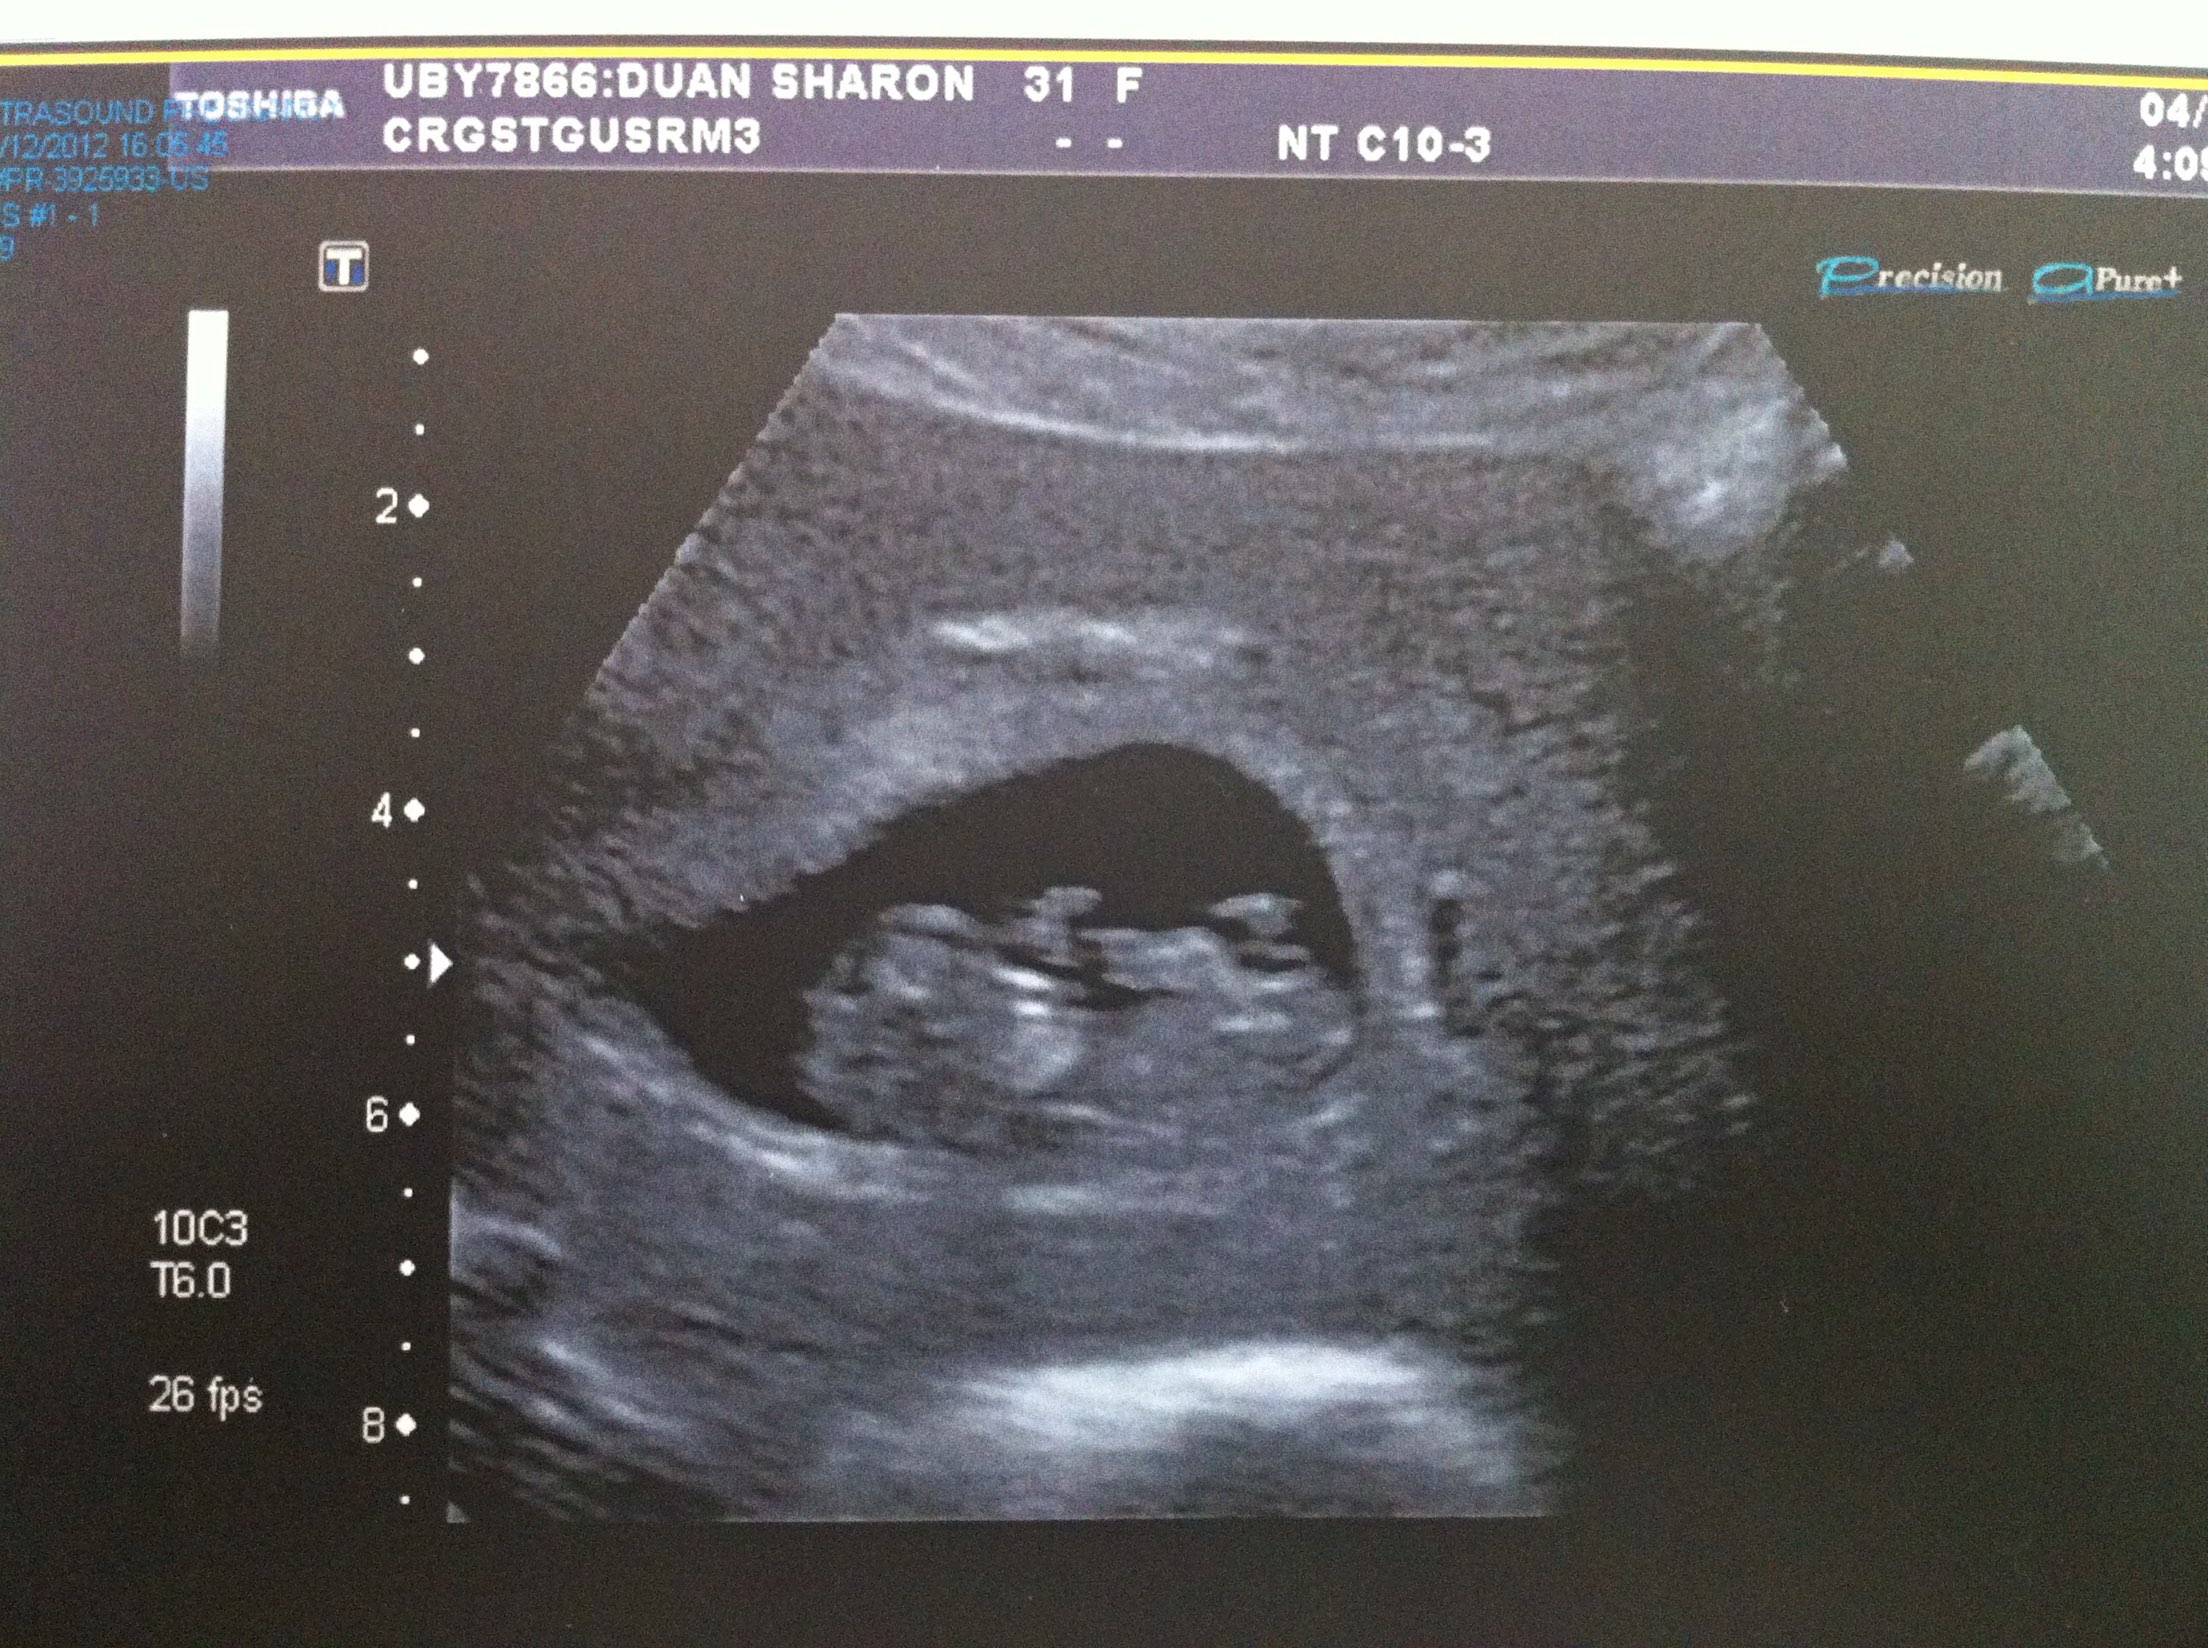

2012年底,我发现自己怀孕了,那时我和老公已经结婚大半年了,作为一个晚婚且属于不易受孕体质的女人,我十分渴望尽快怀上一个孩子,当验孕棒显示阳性时,我激动得不知道该哭还是该笑。第一次在B超中看到他的轮廓时,我和老公都流泪了,那一刻感觉生命如此神奇,我们真的要有自己的孩子了。